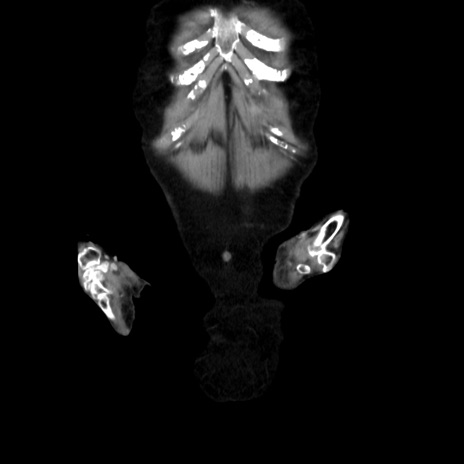

【症例】90歳代女性

【主訴】腹痛・嘔吐

【現病歴】 食欲低下、嘔吐があり昨日他院受診。肺炎と診断され入院となる。入院後より腹部全体に圧痛あり。胃管留置され経過みていたが、症状持続するため、

当院転院となる。

【既往歴】胸椎圧迫骨折、胆石症

【身体所見】腹部:中央に激痛あり、圧痛あり、反跳痛不明

【データ】WBC 17100、CRP 18.82

横断像